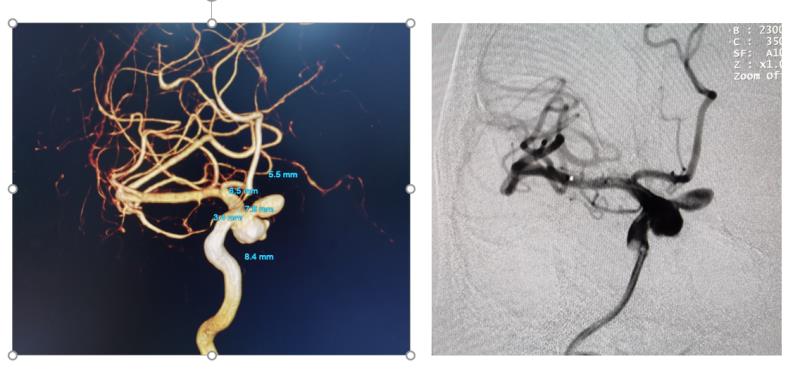

術前

家住柳州的吳某因“右眼視物模糊2月余,檢查發現顱內動脈瘤1天”住入我院神經外科,患者因右眼視物模糊曾多次在外院及眼科就診,視物模糊癥狀均未見好轉,反而呈加重趨勢,并伴隨眼球逐漸突出,后到我院神經內科門診就診,陳紅主任醫師為患者開具了頭顱MRA血管成像檢查,檢查結果提示為:右側頸內動脈床突段巨大動脈瘤,瘤體大約15mm,瘤頸寬,瘤體分葉狀不規則,有明顯子瘤形成,有隨時破裂的風險。陳紅主任醫師立即聯系我神經外科介入組將該患者收入院治療。由神經外科牽頭組織MDT術前討論,討論一致認為:該患者病變復雜,傳統的彈簧圈栓塞或支架輔助彈簧圈栓塞效果不理想,復發率極高,比較適合應用“血流導向裝置(Pinpeline)”來治療該疾病。在征得家屬理解并簽字同意后,于4月28日由神經外科介入組團隊為患者實施了該手術。手術歷時2小時,術中通過5G網絡,連線北京天壇醫院-賀紅衛教授實時指導,手術非常順利,成功控制了病魔,使患者得到治愈。出院時患者及家屬非常激動,還給神經外科醫務人員贈送了錦旗和感謝信。